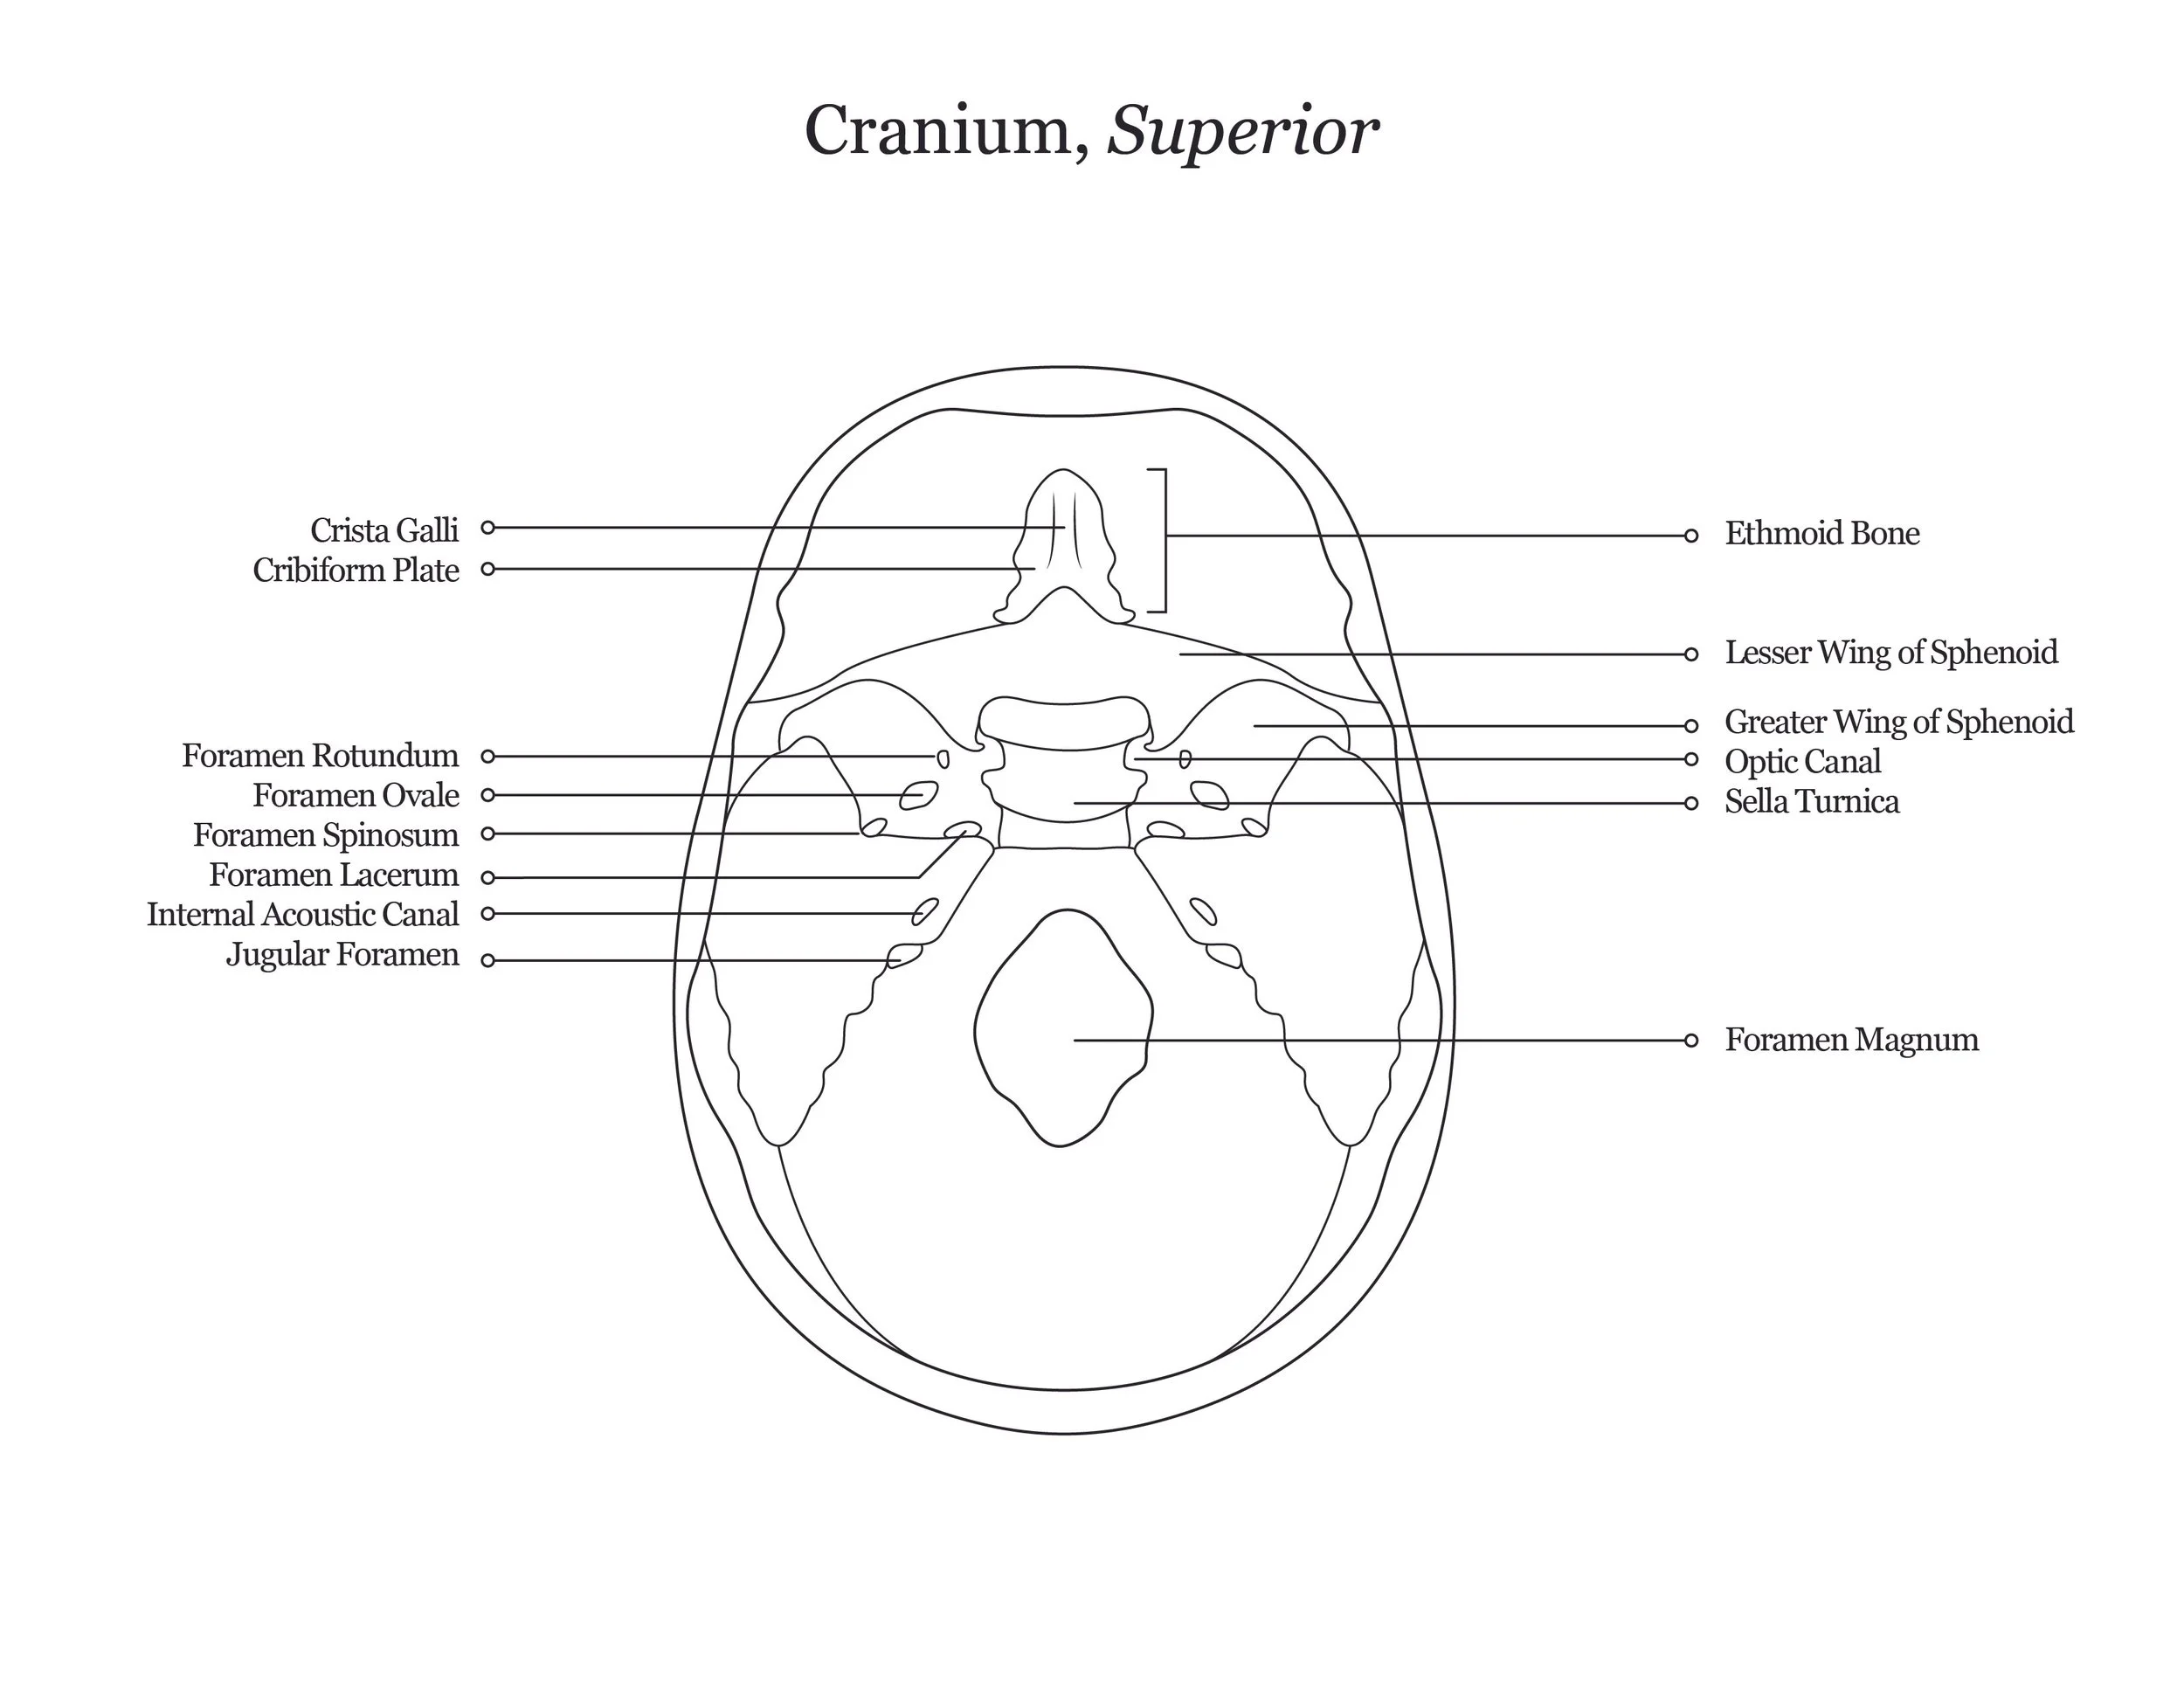

A series of anatomical illustrations created for Arcadia University’s Biology Department.

This project involved illustrating a series of diagrams for a cat dissection manual, focusing on skeletal and muscular anatomy. I consolidated multiple reference sources and firsthand specimen observation into a cohesive visual system for instructional use. Illustrations were refined iteratively to ensure anatomical accuracy, consistency, and clarity for students.